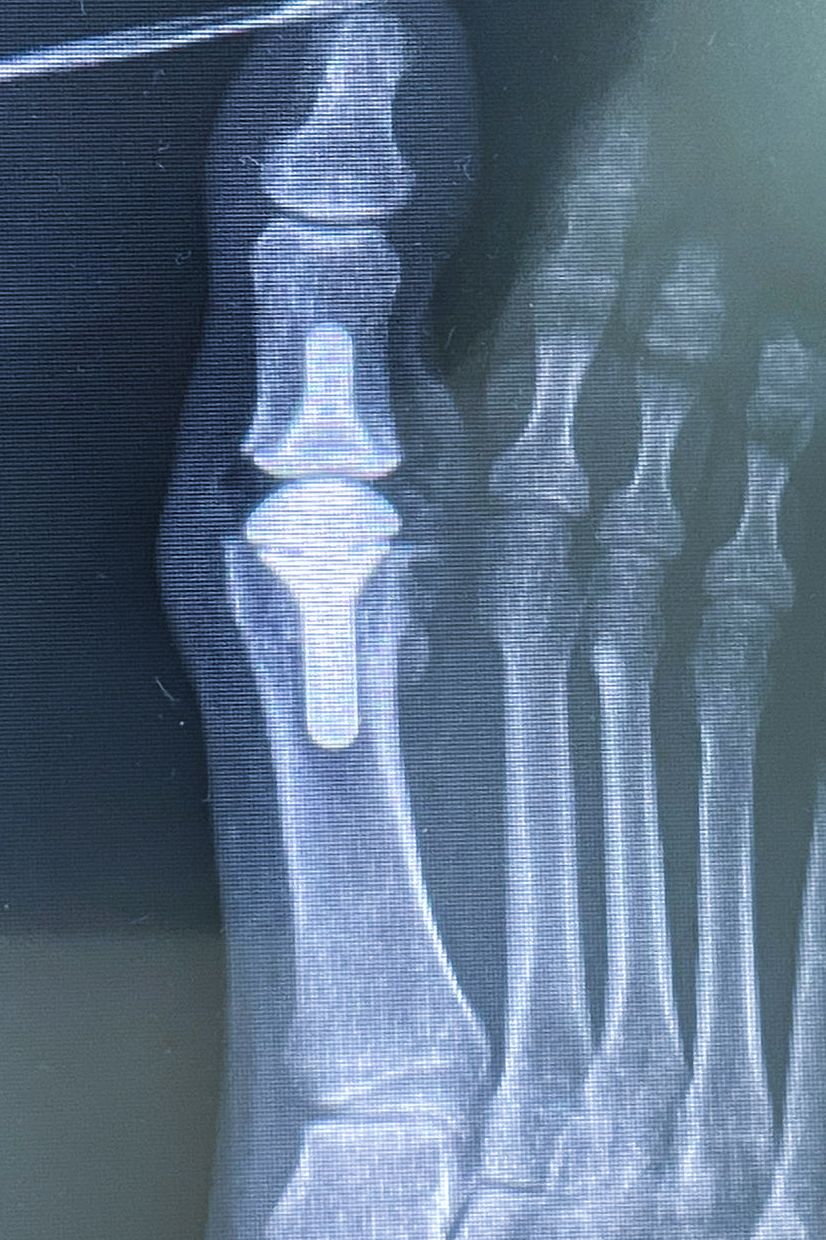

Reducción ortopédica e inmovilización de fracturas y/o luxaciones

La fracturas en la mano deben ser tratadas por manos expertas, puesto que, un mal manejo tendrá siempre consecuencias catastróficas. La mano, para ser funcional, debe ser fuerte, estable, móvil, sensible, no dolorosa y estéticamente bella. Una mano que no cumpla con estas caracteristicas simplemente será inservible en mayor o menor grado para el paciente. Nuestra formación y experiencia nos permite realizar diagnósticos y tratamientos adecuados a cada paciente con el fin de que pueda recuperar su calidad de vida y función.